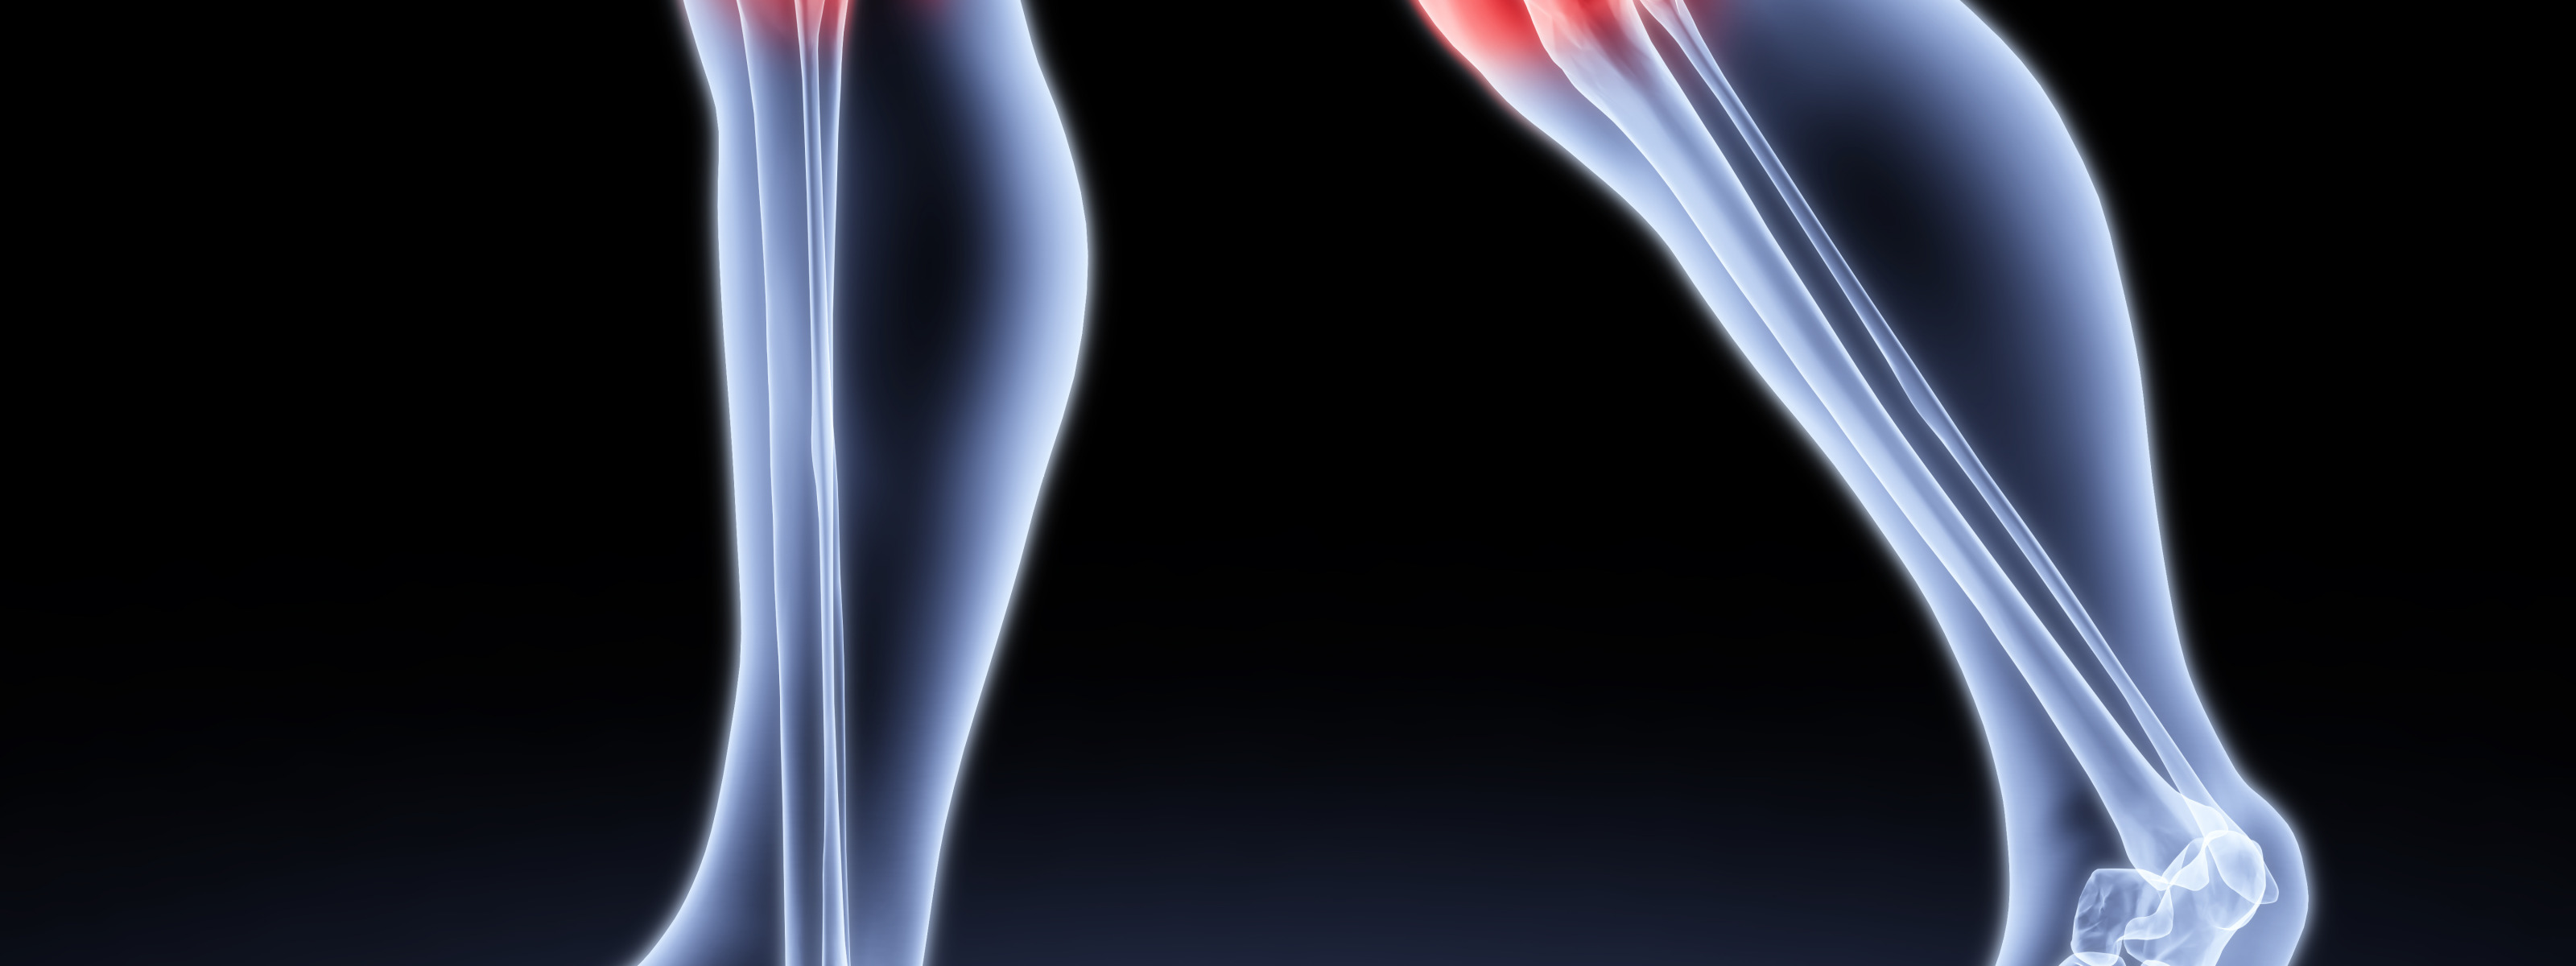

Супрапателлярный импиджмент коленного сустава: симптомы и лечение